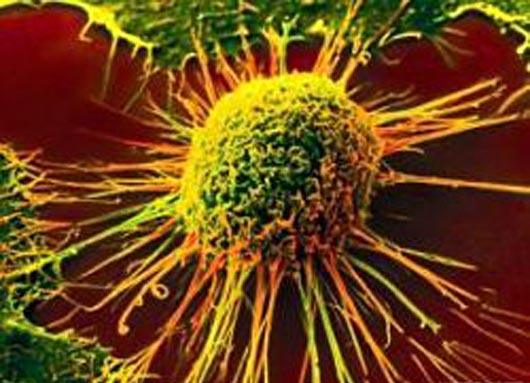

Il mesotelioma nasce dalle cellule del mesotelio (cellule mesoteliali) e può avere origine in quattro zone del corpo: nel torace, nell’addome e, molto raramente, nella cavità attorno al cuore e nella membrana che riveste i testicoli. Il principale fattore di rischio nel mesotelioma è l’esposizione all’amianto: la maggior parte di questi tumori riguarda infatti persone che sono entrate in contatto con tale sostanza sul posto di lavoro.

Si tratta di una rara, ma letale forma di cancro: il tasso di sopravvivenza a cinque anni per i pazienti con diagnosi della malattia è del cinque/ dieci per cento. Anche se la chirurgia può aiutare alcuni pazienti con stadio precoce del mesotelioma, gli attuali trattamenti per i pazienti con mesotelioma avanzato, non sono efficaci.

I ricercatori del Programma Internazionale Mesotelioma presso il Brigham and Women’s Hospital (BWH) si occupano dei pazienti affetti da mesotelioma da circa 25 anni e, parallelamente,stanno studiando la malattia in laboratorio per capire meglio la sua biologia e sviluppare strategie di trattamento per indirizzare le sue vulnerabilità. In un’analisi genomica completa che ha utilizzato più di 200 campioni di tumori, i ricercatori della Brigham and Women Hospital e scienziati provenienti dal Genentech, hanno trovato alterazioni genetiche precedentemente sconosciute, tra cui alcune che possono essere clinicamente trattate e altre che possono migliorare la diagnostica, screening e previsioni sugli esiti della malattia.

In collaborazione con i colleghi del Genentech, i ricercatori hanno analizzato 216 campioni di mesotelioma pleurico maligno (MPM) e confrontato il DNA e RNA con tessuto normale. Essi hanno scoperto più di 2.500 alterazioni e identificato 10 geni mutati in modo significativo. Inoltre hanno individuato la presenza di cellule immunitarie nel sito del tumore. Alcune delle alterazioni genetiche trovate suggeriscono che le terapie mirate, come un inibitoree BCR-ABL-1, potrebbero essere utili per il trattamento di pazienti con questo tumore. Altre alterazioni e la presenza di particolari obiettivi del sistema immunitario potrebbero servire come marcatori per aiutare i patologi a diagnosticare con precisione il mesotelioma e predire quali pazienti avranno scarsi o migliori risultati. Lo studio ha anche analizzato i tumori per l’espressione di PD-L1, un obiettivo dell’ immunoterapia del cancro e ha scoperto che un sottotipo del mesotelioma, potrebbe essere un buon candidato per la terapia anti-PD-L1.